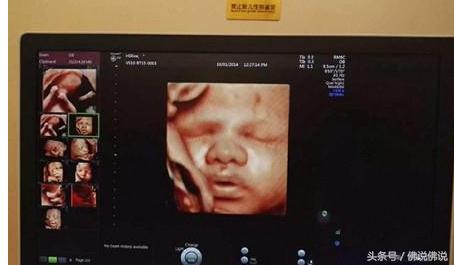

四维彩超供给了包含腹部、血管、小器官、产科、妇科、胎儿彩超图泌尿科、新生儿和儿科等多范畴的多方面的使用。其结果是:能够显现您未出世的宝宝的实时动态活动图画,或许其它人体内脏器官的实时活动图画。

5、四维彩超查看也被称为“大排畸”查看。换言之,就是能够大范围的判别胎儿是否有缺点。当然,由于胎儿发育进程还没有完,而且现有的机器设备不能十分明晰的看清楚胎儿一切的肢体器官,所以,超声确诊符合率不能达100%。

6、胎儿的某些部位不在超声查看范围内,例如,耳朵、性别、生殖器及颚弓。

7、四维彩超中胎儿四肢的查看,不包含指骨、趾骨的数目。